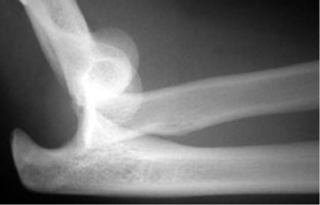

Không cần thiết trong hầu hết trường hợp. X quang thường bình thường. Siêu âm và cộng hưởng từ có thể phát hiện phù nề và các thay đổi của bệnh lý gân như dày lên và bất thường cấu trúc của gân cơ.